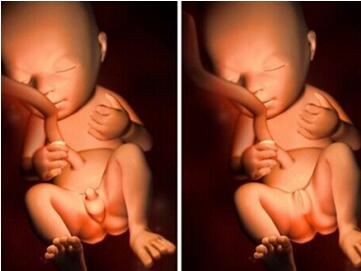

孕期通过B超看男女是通过生殖器来分辨,但一定要到孕15周之后检查结果才准确。因为孕15周后男女胎的生殖器官才有明显差异,能被清晰看出来。

判断方法:女孩生殖器部位是分开往里面发育,而男孩则变成像外突出发育生小jj。